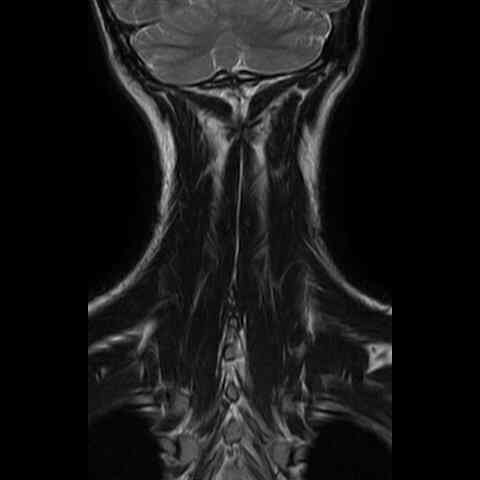

this brain does not look straight...

everything has a twist to it.

perform diy surgery with parasite